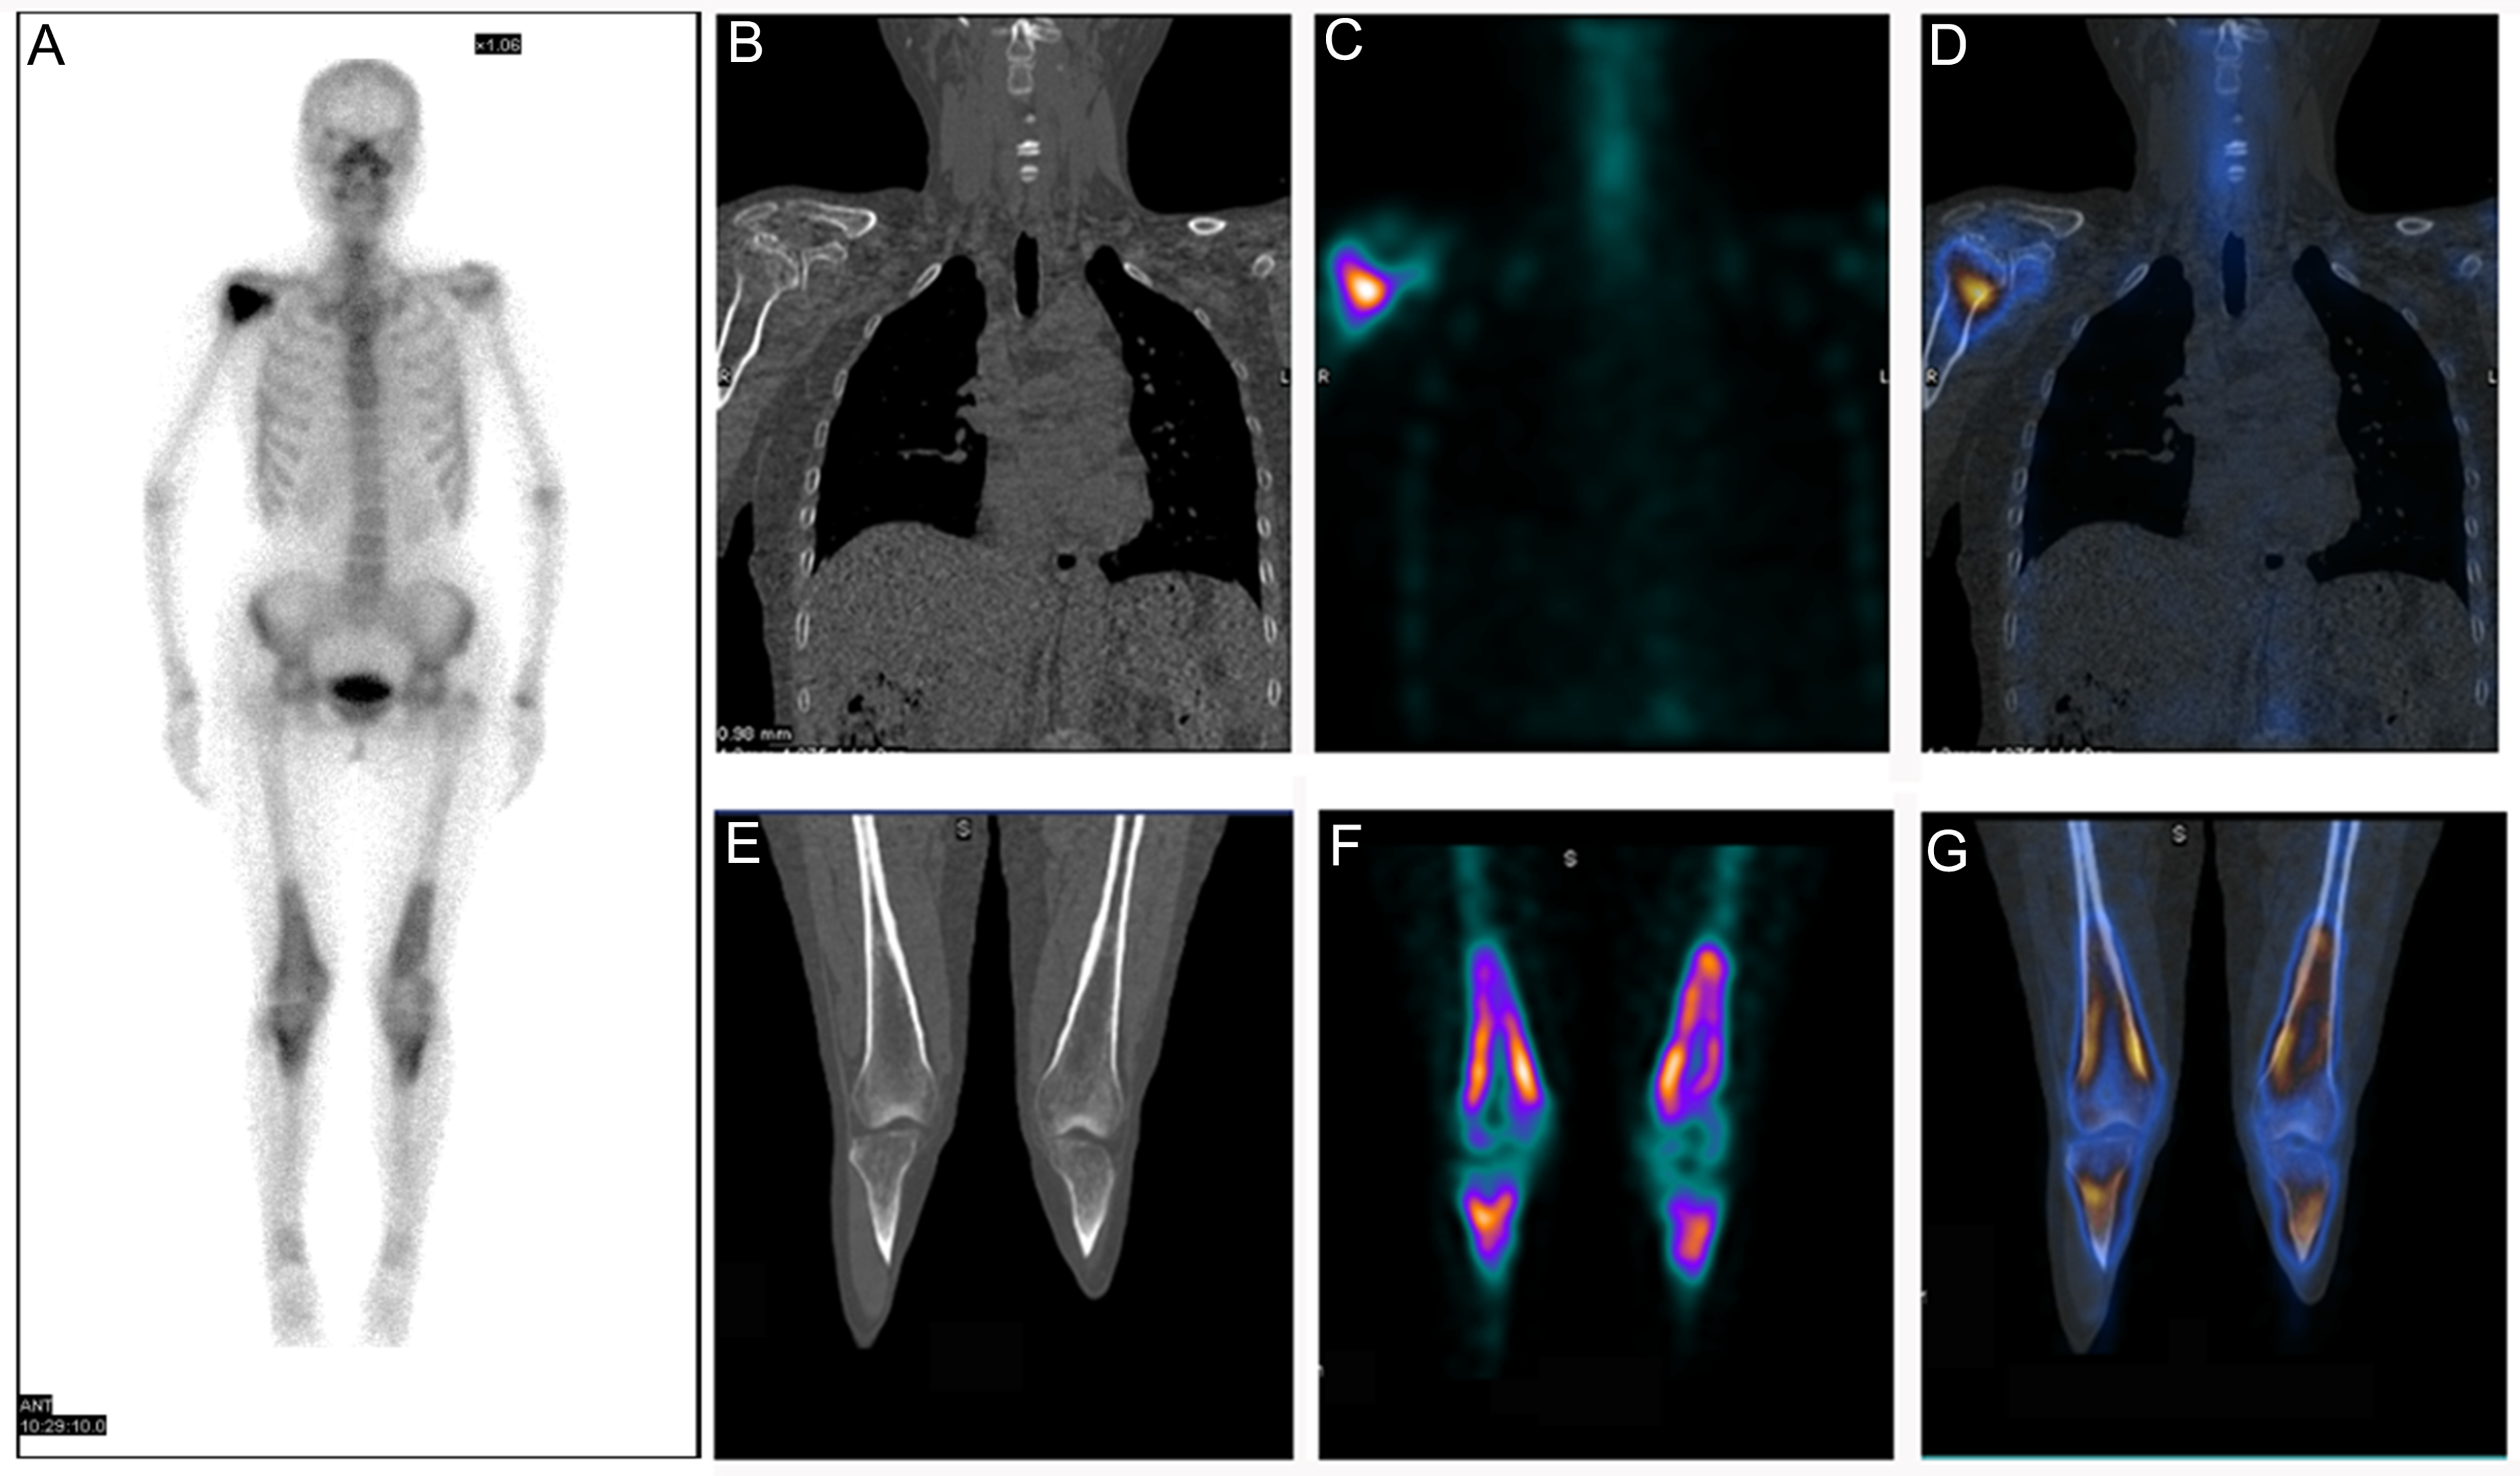

3.5. Erdheim–Chester Disease (ECD)

3.6. Langerhans Cell Sarcoma